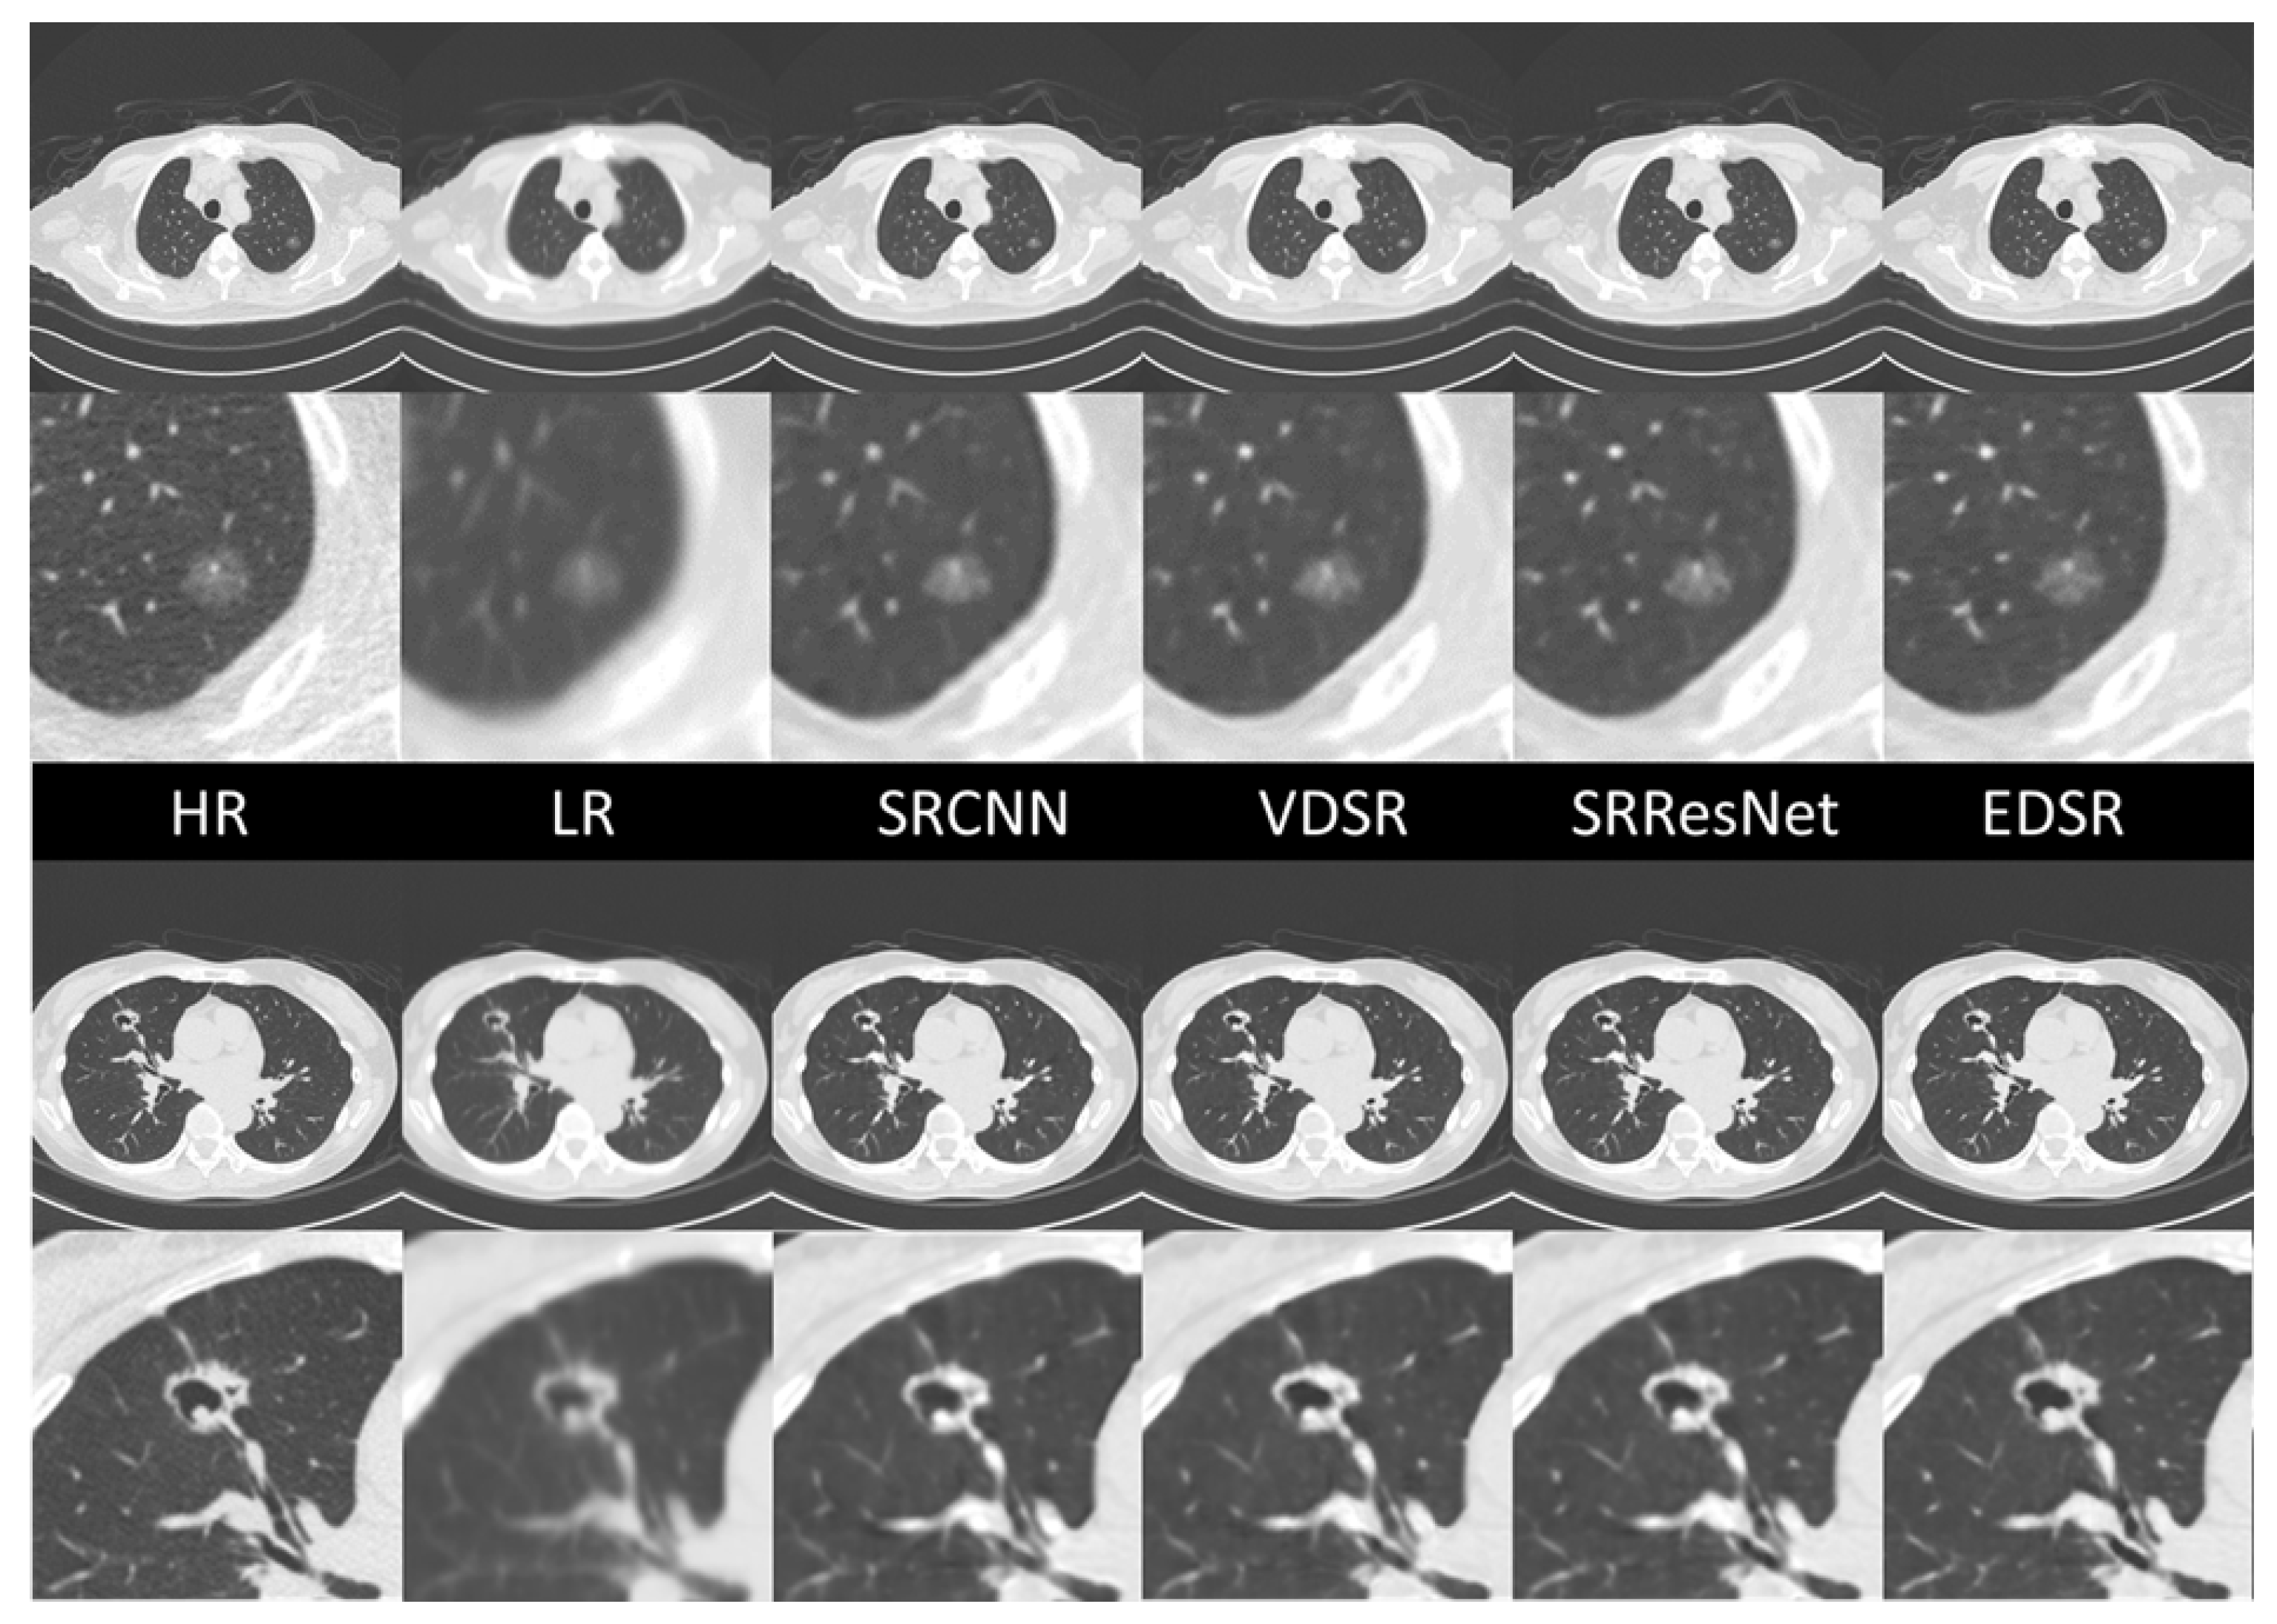

3. Results